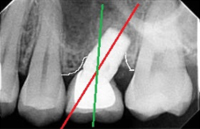

One of the biggest challenges in Dental Implantology is the replacement of the upper central incisor. These CT-scan cross sections of the front upper teeth demonstrate normal anatomical features, which make the job of Dental Implantologist very difficult:

- Paper-thin alveolar bone around the roots of the teeth

- Angulated 15-20 degree long axis of the tooth

- Long anatomical crown (increased lateral load on the future implant compared to the back teeth)

- 4-5 mm overbite (overlap with the lower teeth)